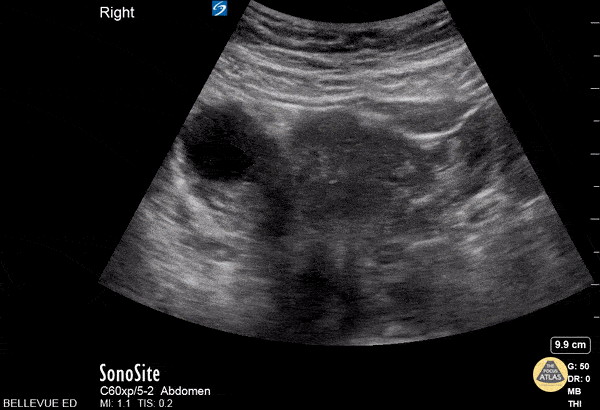

OB/Gyn - Transabdominal Right Adnexa with Ovarian Cyst

In this transabdominal view of the uterus and adnexa we see a thin walled, ovoid anechoic structure on the left side of the screen. This is a simple cyst on the right ovary. As the probe fans, the uterine fundus comes in and out of view medial to the ovary .